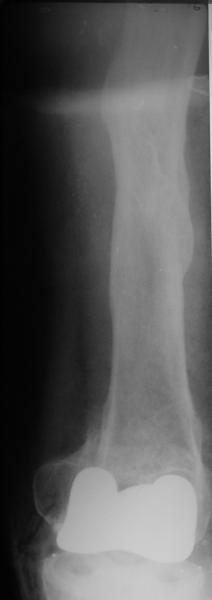

Добрый день! В нашу больничку поступил пациент после бытовой травмы - упал, подвернув ногу. На RG-граммах перелом дистального метаэпифиза бедренной кости. Пациент спутанно рассказывает, где и как он лечился раньше.10 лет назад - коррегирующая остеотомия по поводу деформирующего артроза коленного сустава, 3 года назад в 1 градской больнице г. Москвы выполнено эндопротезирование коленного сустава,площадка большеберцовой кости, со слов пациента, деформировалась около года назад (на фоне остеопороза). Сейчас получил травму в результате падения с высоты собственного роста.Что посоветуете?

на снимке признаки loosening и тибиального и феморального компонентов я думаю нужна ревизия если нет возможностей то артродез и конечно исключить инфекцию . успехов .

Мне представляется следующее: Если дистальный отдел бедра расколот и в сагиттальной и во фронтальной плоскостях, как видно на рентгенограммах, и при этом есть смещение отломков относительно друг друга и бедренного компонента эндоаротеза, разве от может оставаться стабильным? В случае отсутствия проблем с тибиальным компонентом, можно было бы надеяться только на остеосинтез и стабилизацию, но если предполагается ревизия в ближайшие месяцы/год, то не лучше ли за один раз решить несколько проблем?